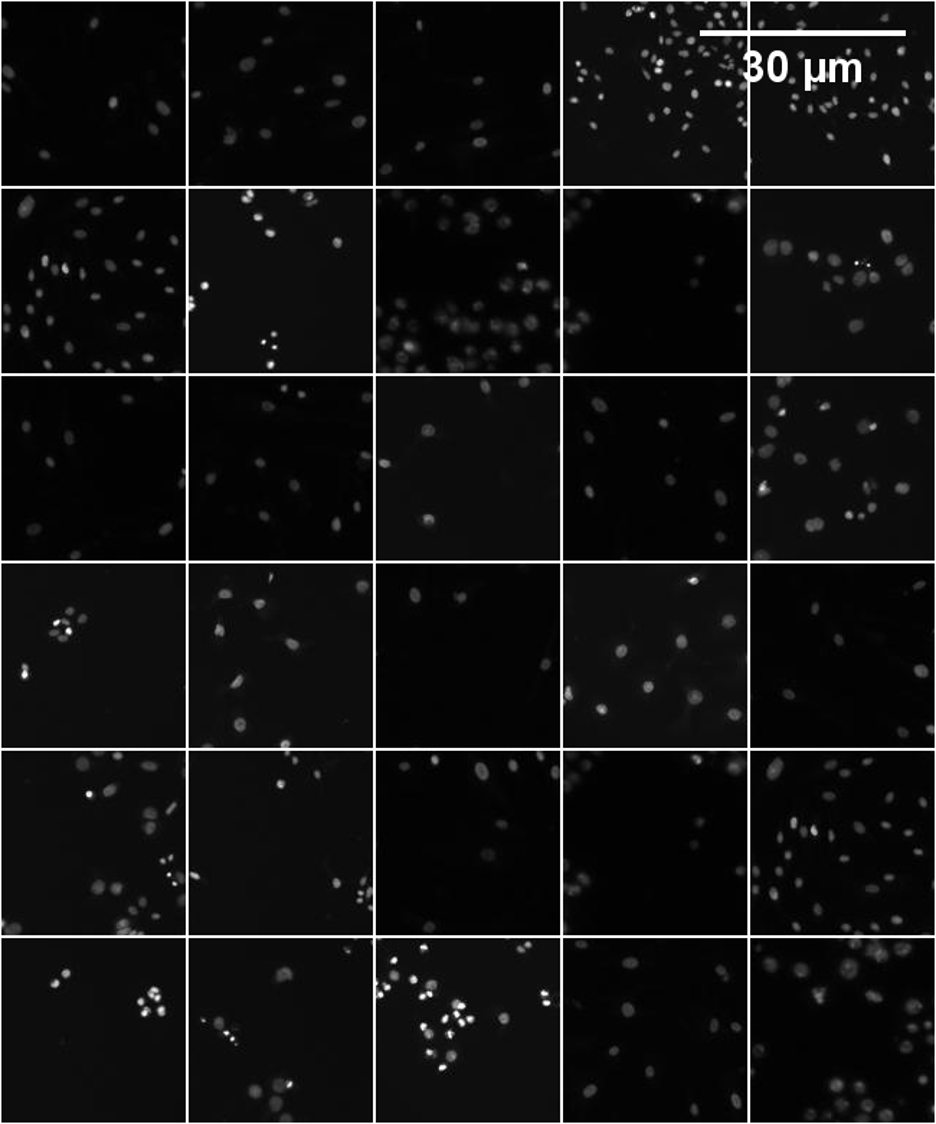

Refer to caption

Figure S17: A sample of the final images created from the StyleGAN2-Diff method (128×\times128 for each sample) using the Kaggle dataset.

Figure S18: A sample of the final images created from the real images (128×\times128 for each sample) using the CAR-T/NK dataset.

Figure S19: A sample of the final images created from the real images (128×\times128 for each sample) using the Kaggle dataset.